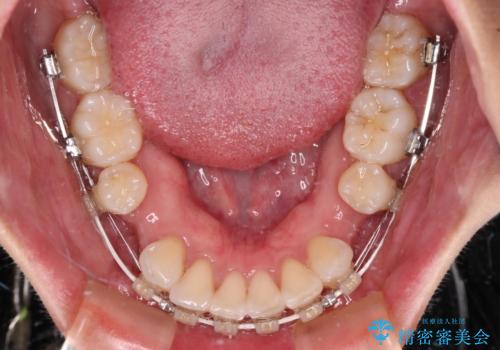

- 矯正装置

- 審美装置

結婚式を行う予定があるとのことで、表側のワイヤー装置で、速やかに治療を終えられるようにしました。